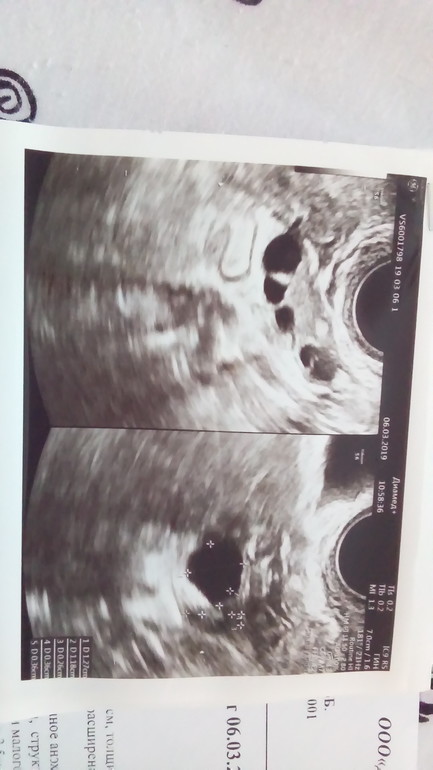

Персистирующий фолликул ли?

ФолликулометрияПо УЗИ на 4день цикла персистирующий фолликул 13*12 мм.

Сверху правый, снизу левый яичник( извиняюсь , перевернуть фото почему то не получилось)

снизу ПФ